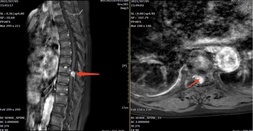

• 骨科手術(shù)機(jī)器人助推我院骨傷科躍進(jìn)精準(zhǔn)治療新高地

77歲的葉阿婆原本在家安享晚年生活,14個(gè)月前開始出現(xiàn)雙下肢麻木乏力,癥狀逐漸加重,軀體麻木感平面逐漸上移,5個(gè)月前出現(xiàn)右下肢抬腿行走都很困難,需扶拐行走,近3個(gè)月甚至出現(xiàn)了二便乏力、排便困難。這讓葉阿婆生活質(zhì)量急劇下降,苦不堪言,當(dāng)葉阿婆的兒女們得知漳州市中醫(yī)院骨傷科是國家臨床重點(diǎn)??票泸?qū)車百余公里前來求診。    骨傷科副主任王慶敏詳細(xì)診查后,考慮葉阿婆的癥狀為胸8/9椎管水平的脊膜瘤壓迫脊髓神經(jīng)引起。增強(qiáng)磁共振清楚顯示椎管內(nèi)...